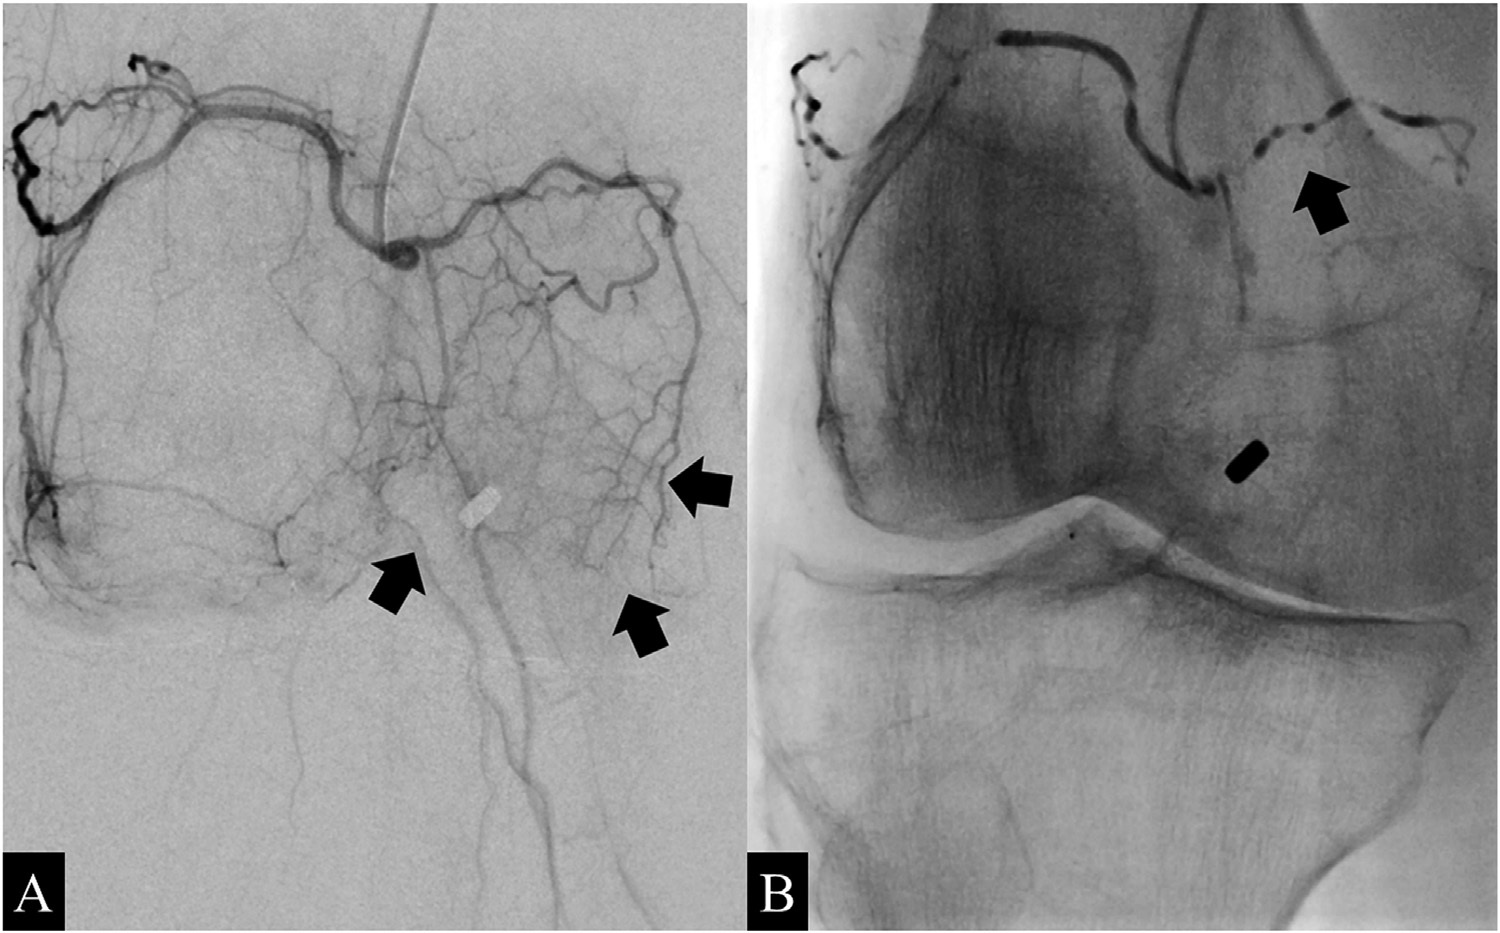

Grad-CAM interpretation of deep-learning-binary predictions. Grad-CAM heat mapping showing areas of highest activation for a control and case prediction made on the knee DEXA images. The regions of the map with the darkest color (purple) represent areas that were less informative in the prediction, while lighter colors (yellow) indicate regions of the image that informed the "case" or "control" prediction the most. We find areas of highest activation are most often on the medial side of the knee joint. Image courtesy of npj Digital Medicine through CC BY 4.0.The researchers then trained the AI model to identify these image-based phenotypes on a separate dataset of 546 images that had been independently annotated by three board-certified orthopedic surgeons. Next, in a test dataset of 110 images, the deep-learning model identified the imaging phenotypes with a sensitivity of 82% compared with clinicians (77%) and a specificity of 95% compared with the clinicians (97%).